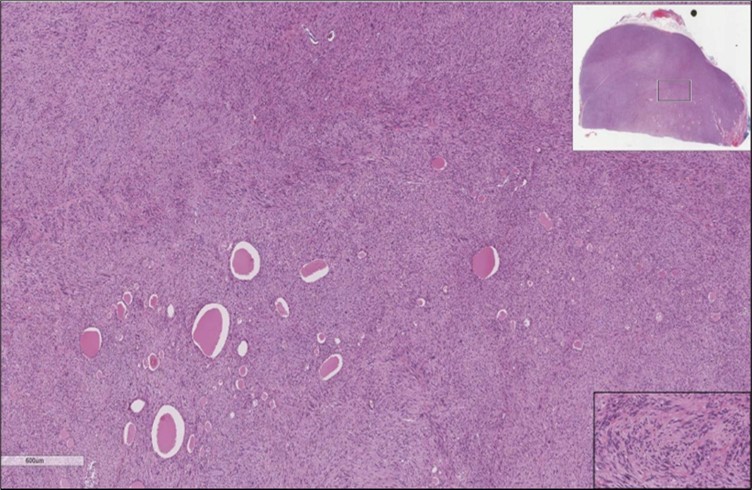

When diagnosing thyroid swelling, imaging studies have been helpful in differentiating malignant from benign tumors with US being used as an initial evaluation tool when assessing thyroid nodules. Tumors are categorized based on composition, echogenicity, shape, margin and echogenic foci into added scores determined by the TI-RADS system, which determines the need for FNA 13. Other imaging modalities include MRI and CT. However; radiological assessment does not distinguish between the types of thyroid cancer, and therefore FNA and biopsy are of crucial importance 3, 6. On a pathologic sample, LMS appears as spindled eosinophilic cells with elongated blunt-ended or cigar-like nuclei arranged in fascicles 2, 7 (Figure 1, Figure 2, Figure 3). Despite the unique microscopic morphology, LMS cannot be distinguished from other spindle cell tumors such as spindle cell variant of medullary thyroid cancer, anaplastic thyroid

Figure 1.Left thyroid Low power of the thyroid gland showing complete replacement of the thyroid by the neoplastic cells (H&E, ×4).

Figure 2.Left thyroid On a Higher power, few thyroid follicles are noted and the lesion is composed of spindle cells with sweeping fascicles (H&E, ×200).

cancer, or other metastatic tumors without further testing with genetic or molecular studies 3, 7. Immunohistochemical testing plays a vital role in differentiating LMS from such similar tumors as it stains positive for vimentin and smooth muscle actin (SMA), and is variably positive for HHF35, desmin (50%-100%), and H-caldesmon 3, 6. Moreover, there were no reported cases where thyroid LMS stained positive for thyroglobulin, cytokeratin, calcitonin, chromogranin, or protein S100 3. Our patient’s left thyroid biopsy showed the characteristic microscopic features and was positive for SMA, desmin, caldesmon, P63 with patchy EMA (Figure 1, Figure 2, Figure 3, Figure 4) as well as her liver biopsy (Figure 5, Figure 6, Figure 7); whereas her right thyroid showed clear papillary thyroid cancer cell features (Figure 8, Figure 9).